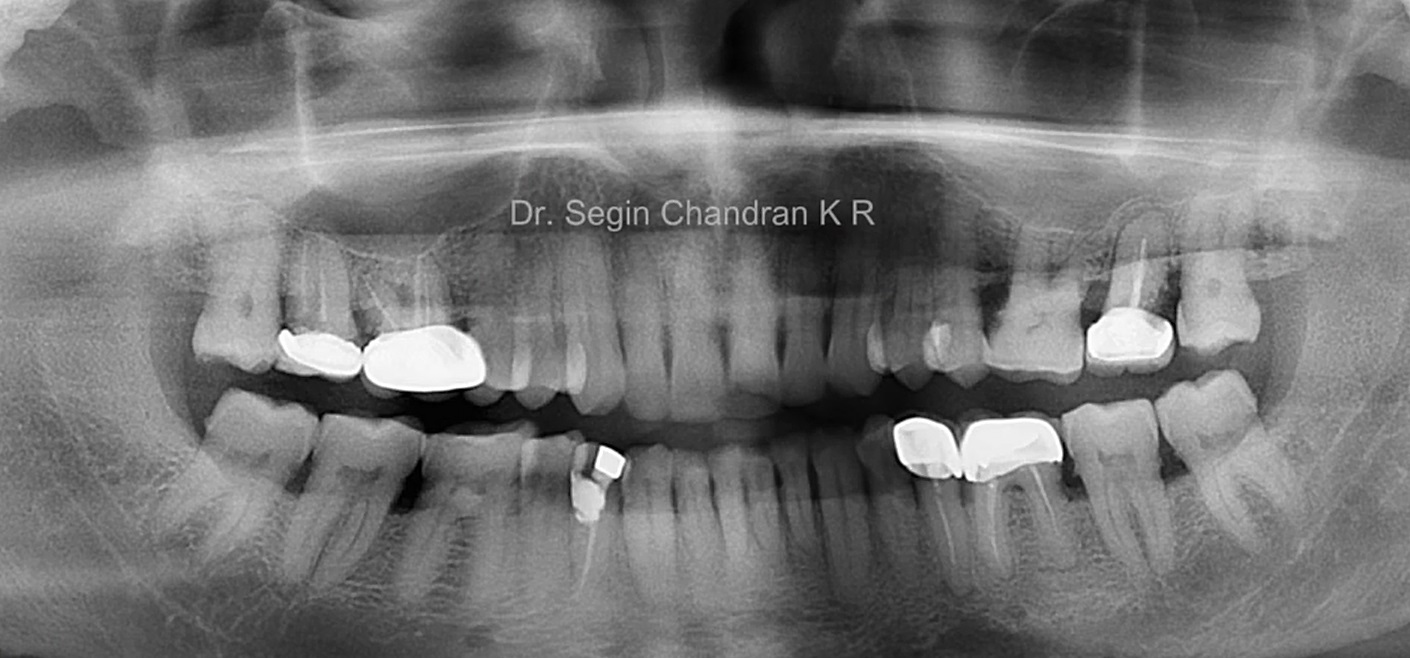

Root Membrane with R2GATE

#12,#21,#23,#26,AnyRidge,Digital Guided Surgery,Dr. Konstantinos Siormpas,Flapless,Guided surgery,Immediate Placement,Maxillary Anterior,Maxillary Posterior,R2GATE Guide,R2GATE Universal Kit,Root Membrane,Root Membrane Kit,video,Xpeed